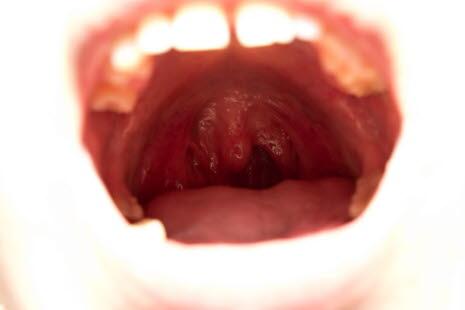

Munntørrhet er en hyppig plage. Årsaken kan være underliggende sykdom eller bivirkning av medisin. Munntørrhet disponerer for soppinfeksjon og tannråte.

I tillegg til å være ubehagelig gir munntørrhet også større risiko for å få soppinfeksjon i munnen og for å utvikle hull i tennene. Det er heldigvis en rekke ting du selv kan gjøre for å forhindre dette: